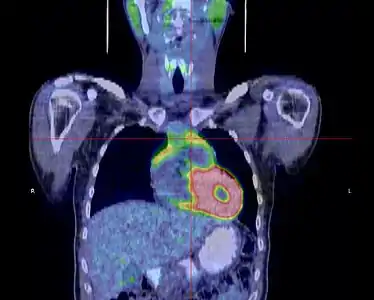

La place du TEP scanner dans le diagnostic des thymomes est encore débattue[31]. S'il existe bien une hyperfixation de la tumeur, son rôle dans le diagnostic de l'extension locorégionale reste à préciser[33].

- Thymome de type B1 en TEP scanner

Coupe transversale. Les trois clichés sont extraits du même examen.

Coupe transversale. Les trois clichés sont extraits du même examen. Coupe frontale ; la tumeur est à l'intersection des lignes rouges.

Coupe frontale ; la tumeur est à l'intersection des lignes rouges. Coupe sagittale ; la tumeur est à l'intersection des lignes rouges.

Coupe sagittale ; la tumeur est à l'intersection des lignes rouges.